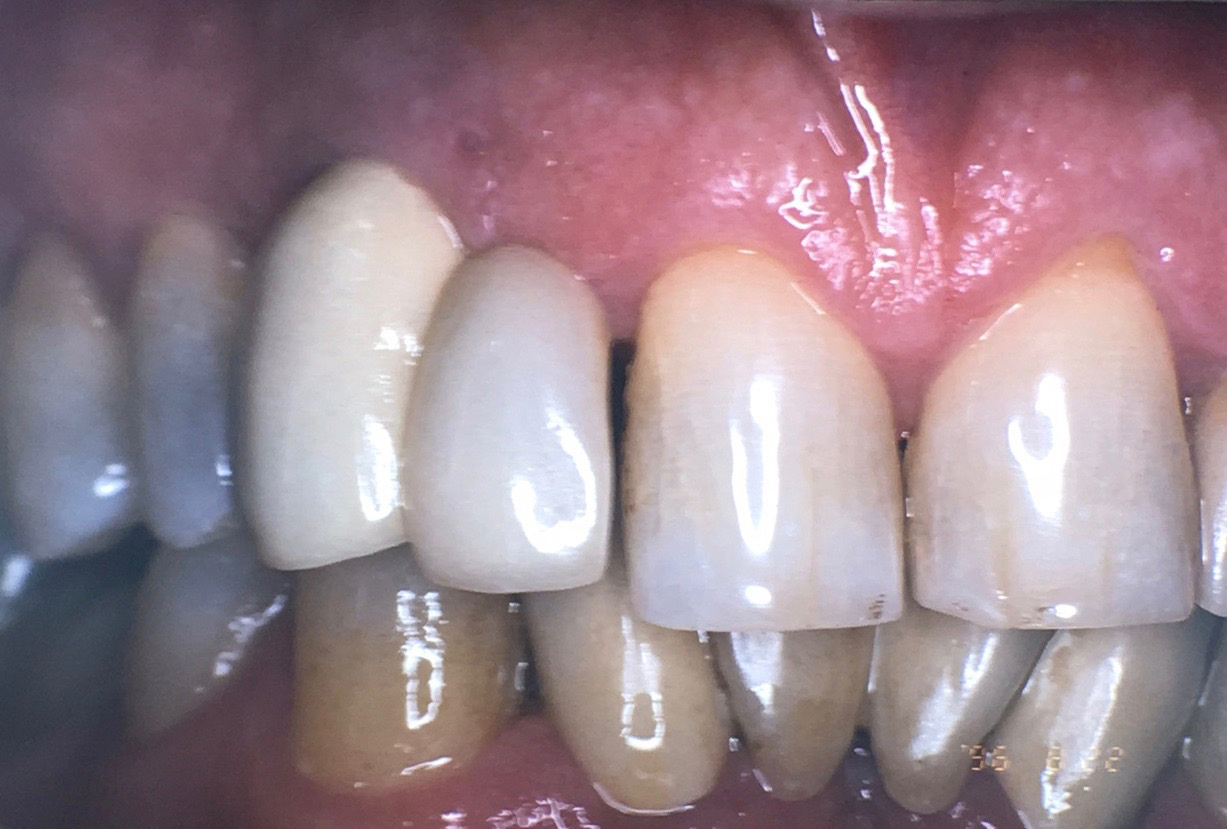

Fig 8. Loss of restoration and subsequent tissue overgrowth from broken abutment screw as shown in the radiograph (Fig 9).

Figure 8

Fig 9. Radiograph depicting fractured screw inside of the implant.

Figure 9